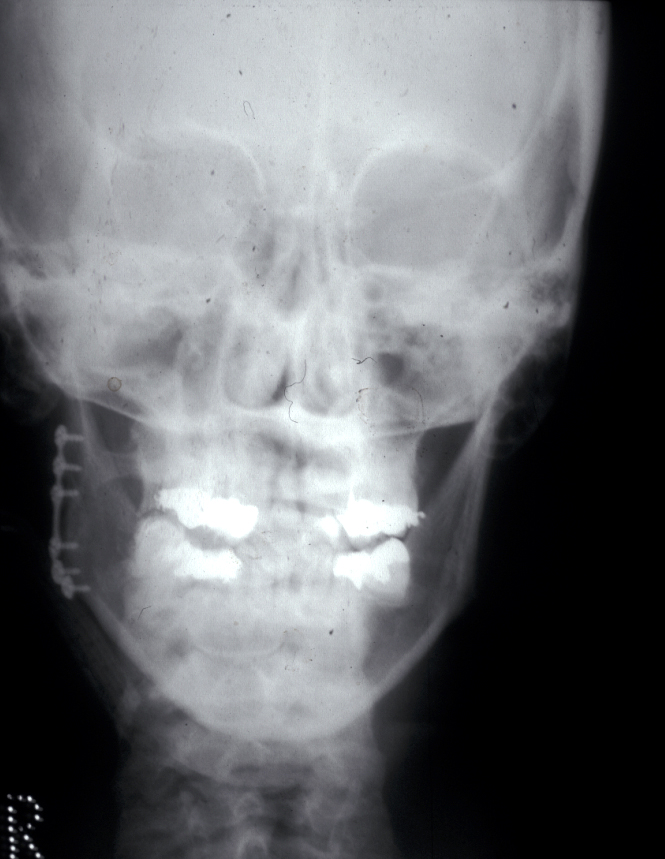

Joint replacement is a significant operation for symptomatic irreparably damaged joints. Costochondral rib graft (see Figure 7) or customised prosthetic joints are used. The unpredictability of costochondral rib (a third are stable, a third resorb and a third overgrow) and refinements to customised prostheses have moved almost all jaw joint replacement for terminal joint damage to these devices (see Figure 8).

Figure 8: Customized total TMJ replacement.